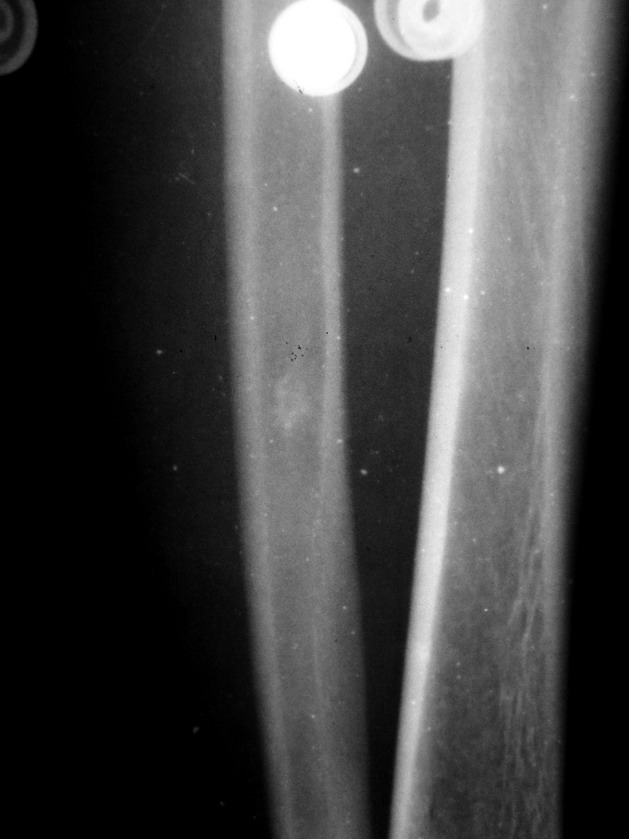

患者 男26岁 左胫腓骨扭伤

1、外踝骨折。

2、腓骨下端内生骨瘤,即骨岛。